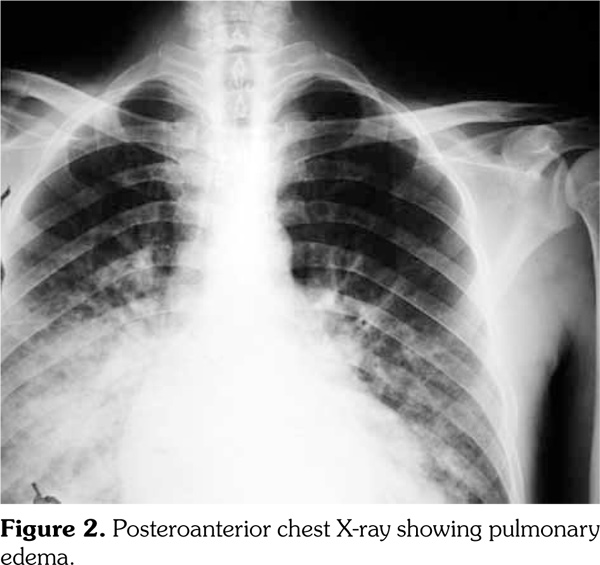

During the follow-up, the patient developed shortness of breath, orthopnea and paroxysmal nocturnal dyspnea. He was referred to the intensive care unit and followed for acute pulmonary edema (Figure 2). Nitroglycerine and furosemide infusions were started and his clinical symptoms improved. Laboratory work-up for anemia etiology revealed 1+ direct Coombs’ test, low iron level and iron-binding capacity and a high ferritin level (Table 1). Analysis of peripheral blood smear showed no signs of hemolysis. Patient’s findings were consistent with anemia of chronic illness. One unit of red blood cell transfusion was performed to increase hemoglobin level to 10 g/dL. A follow-up TEE was performed two weeks later to assess response to treatment. Vegetations were still present in aortic non-coronary (15x6 mm) and coronary (3x4 mm) valves. Surgical operation was preferred after consultation with Cardiovascular Surgery and Cardiology Departments. During the operation, aortic valve with vegetation was resected and replaced with a prosthetic valve (Figure 3). Additionally, mitral valve showing advanced insufficiency was resected and replaced with a prosthetic mitral valve. During the follow-up, the patient was heparinized and warfarin was initiated. Creatinine levels followed a stable level at about 2.5 mg/dL. He did not have fever during follow-up and his treatment for infective endocarditis was completed in six weeks. Renal biopsy was offered but the patient did not consent.

Cardiac complications of brucellosis are not common. Less than 2% of patients with brucellosis shows cardiovascular involvement and the most common form is endocarditis.(2,7-9) Myocarditis and heart failure develop rarely.(10) Brucella pericarditis without endocarditis was reported in a limited number of patients.(11) Although the risk of developing endocarditis in brucellosis is low, deaths from brucellosis are majorly caused by endocarditis and associated development of congestive heart failure. Usually aortic valve is affected, requiring urgent surgical valve replacement.(12) Heart failure, rhythm disorders or acute pulmonary edema may occur in patients as a result of cardiac involvement. Aortic valve endocarditis may lead to acute myocardial infarction. The mechanism for cardiac damage is unclear but it may be related directly to the culprit microorganism or develop as a result of accumulating local immune complexes.(13)